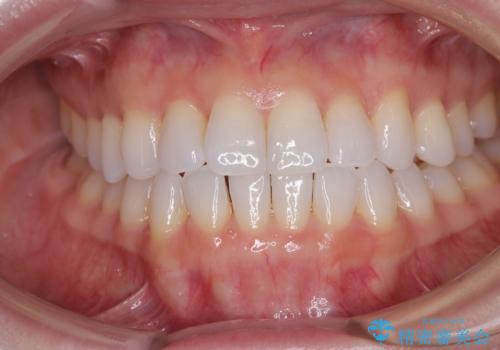

前歯のデコボコをインビザラインで綺麗に

- 上下前歯の叢生を気にして来院された患者様です。

インビザラインでの治療を希望されていて、デコボコの程度が中等度であり、安価なパッケージにて対応可能と判断されたため、インビザライン・モデレートを用いて矯正治療を行うこととしました。